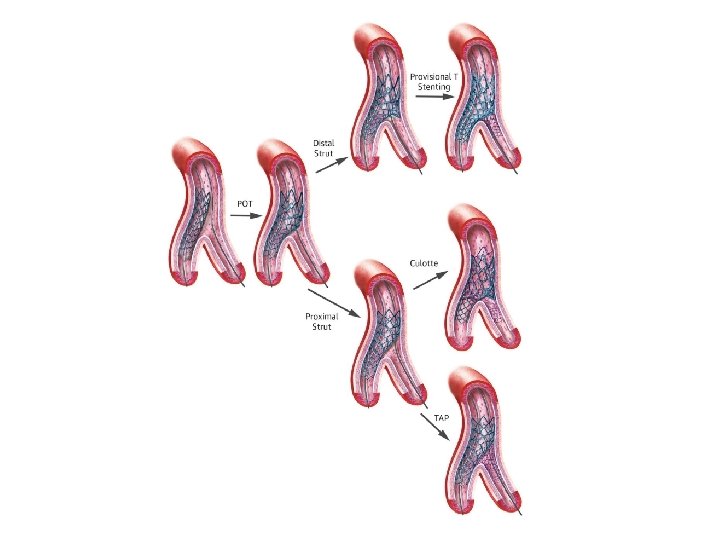

Stenting techniques 1)Provisional • Mainvessel stenting ± side branchangioplasty (Provisional) Tstenting, • TAP, • REVERSEINTERNAL CRUSH • REVERSECULOTTE. 2) elective • Culotte-stenting • Crush technique (reversecrush) T TECHNIQUE AND TAP • V STENTING • Y STENTING(SKS technique)

Provisional stenting strategy 1. Both branches are wired starting with the most difficult one 2. MB is stented (stent sized according to MB distal reference) and SB wire is jailed 3. The stent is post-dilated using the Proximal Optimization Technique (POT) to maximize stent apposition 4. Stent is now well apposed proximally, while the SB is partially covered by scaffolding 5. MB wire is pulled back and reinserted through the most distal strut of the SB opening scaffold 6. Jailed wire is removed and re-inserted in the distal MB (with a formed loop at the distal end) 7. The Kissing Balloon inflation is done to optimize side branch flow and access 8. Final result (if suboptimal, can then place additional stents)

Modified T technique

Culotte technique

� It provides near-perfect coverageof the carina &SBostium atthe expense of an excessof metal covering in proximal. MB. � Bestimmediate angiographic result &theoretically itmayguarantee a more homogeneous distribution of struts &drug. � Canbeused in all bifurcation lesions irrespective of bifurcationangle. � Open-cell stents arepreferred when the SBdiameter is >3 mm. � Disadvantages – � Complexity in the rewiring of both branches through the stentstruts, � Not advisable if both branches aredissected afterpredilatation.